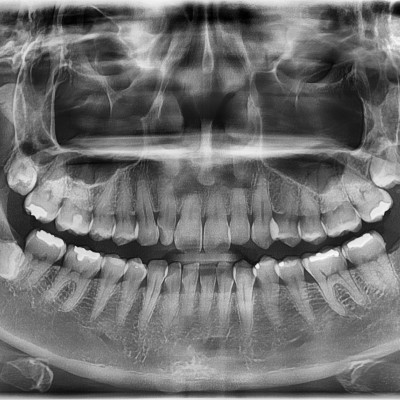

#18,28,38,48 사랑니 발치 #18,28,38,48 사랑니 발치 구강 외과 전문의가 당일 발치했습니다. ------------------..

작성자 이턱이 작성일 02-02 조회 4